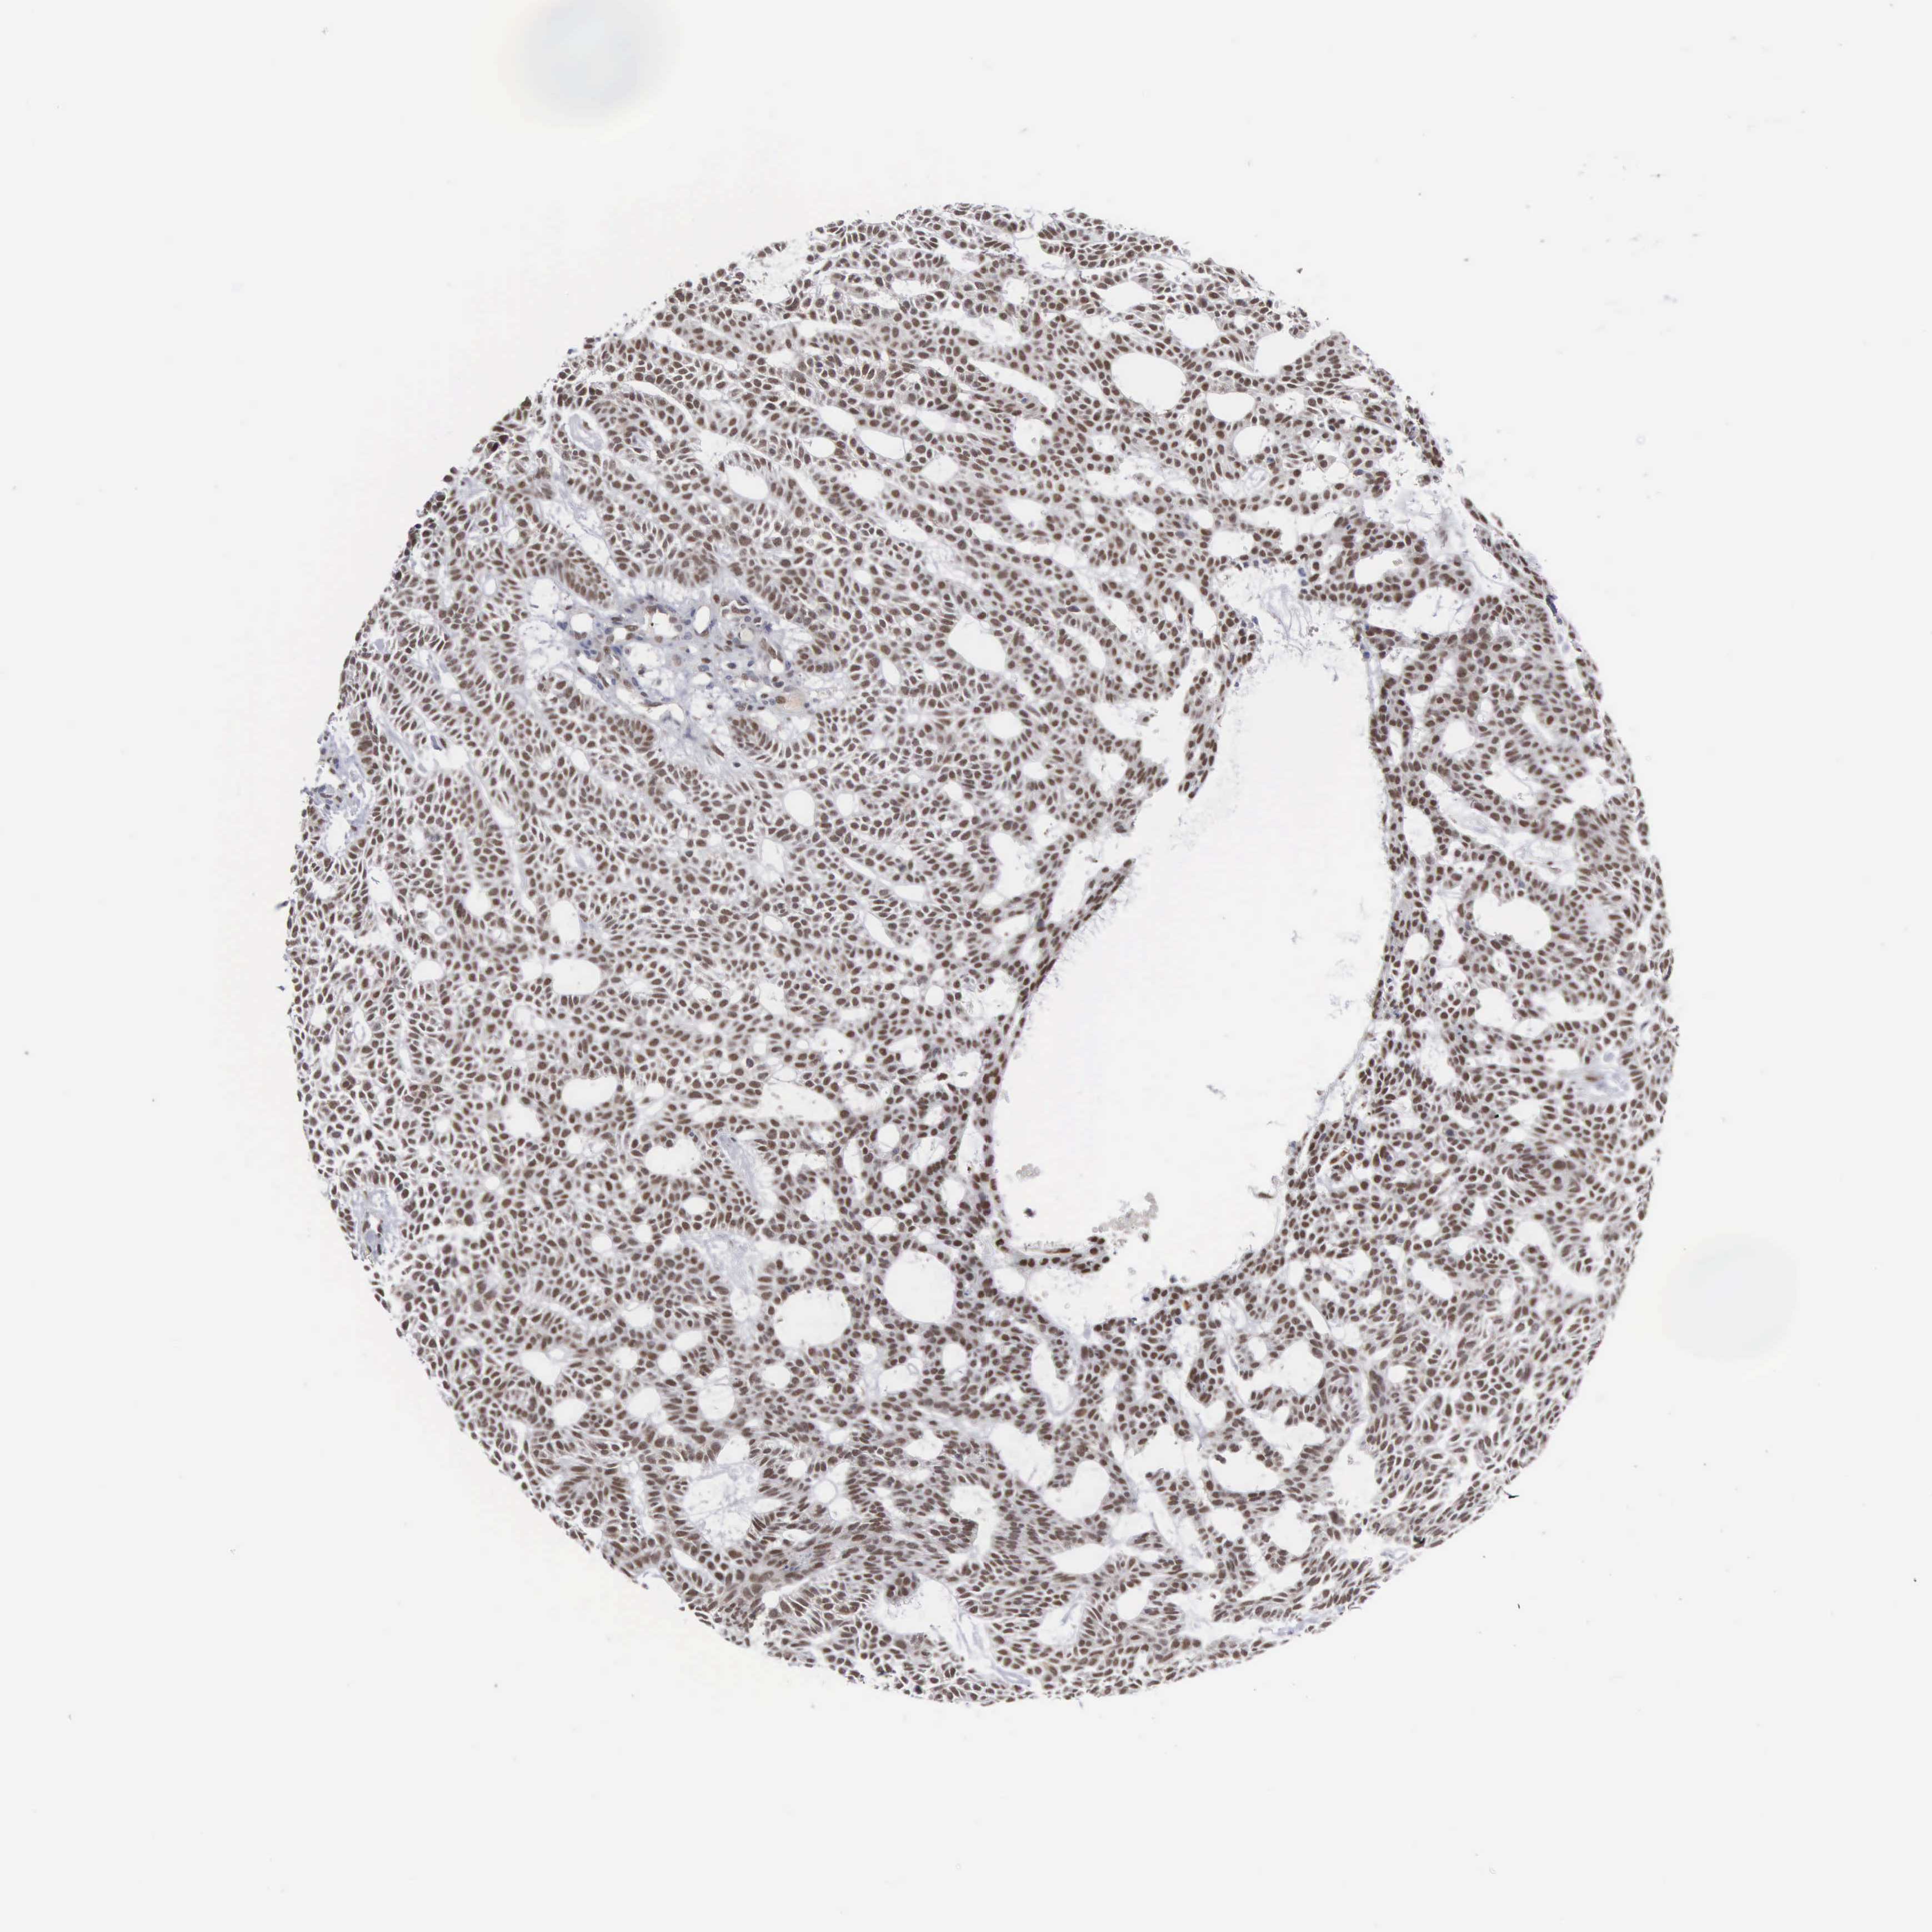

Basal cell and squamous cell cancer

SKIN CANCER - Protein expressioni

A mouse-over function shows sample information and annotation data. Click on an image to view it in a full screen mode. Samples can be filtered based on level of antibody staining by selecting one or several of the following categories: high, medium, low and not detected. The assay and annotation is described here.

Antibody stainingi

Antibody staining in the annotated cell types in the current human tissue is reported as not detected, low, medium, or high, based on conventional immunohistochemistry profiling in selected tissues. This score is based on the combination of the staining intensity and fraction of stained cells.

Each image is clickable and will lead to virtual microscopy that enables deeper exploration of all samples and also displays staining intensity scores, fraction scores and subcellular localization as well as patient and tissue information for each sample.

Antibody HPA000943

Staining

High

Strong

Quantity

Location

Nuclear

Squamous cell carcinoma, NOS

Basal cell carcinoma